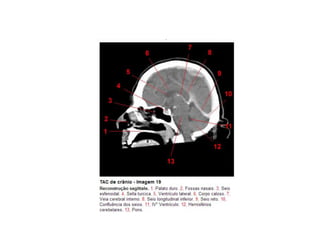

Anatomia E Protocolo Tomografia Computadorizada de Crânio PPT